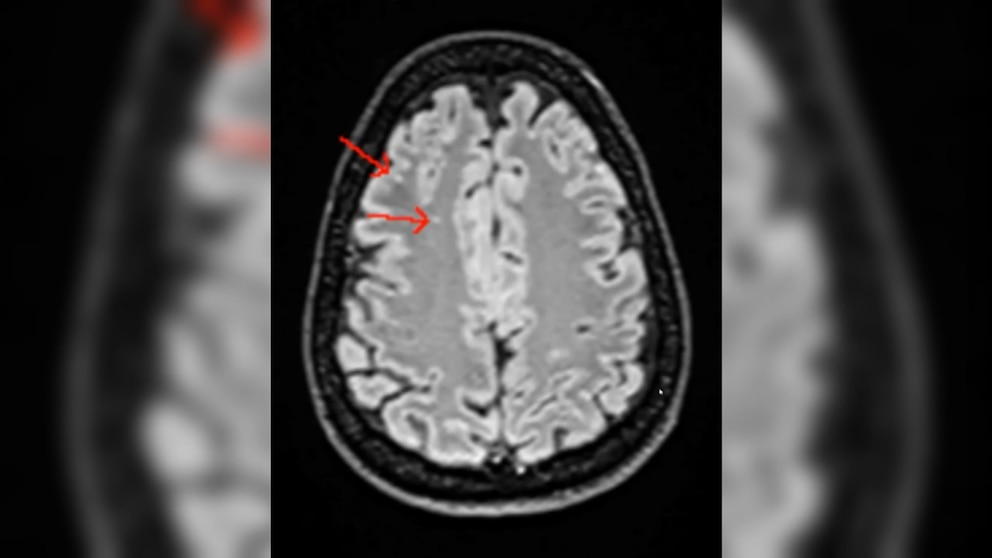

I went ahead with the scan and spent about an hour in the Silicon Valley facility. Two days later, I received access to an online dashboard showing my results. Reading them myself there were some findings that scared me: Some lesions in my brain and degenerative arthritis in my neck and spine (yes, I Googled all the issues and regretted it). But overall, there was no indication of cancer or serious disease, and that was a relief.

As part of Prenuvo's premium package, a Prenuvo doctor met with me over Zoom to discuss the scan. This was incredibly helpful and put many of my fears to rest. The brain lesions were not of concern to the doctor, and considering my history playing a full-contact sport (15 years of rugby), the doctor said this was a very good brain scan. He said the arthritis was typical wear and tear for an athlete, but he was concerned with the MRI of my nose showing a seriously deviated septum. He wanted me to be rechecked for sleep apnea -- I do not have apnea per my most recent sleep study, but I do snore -- and he advised me to stay vigilant and get rechecked if I had any indication of reduced sleep quality.